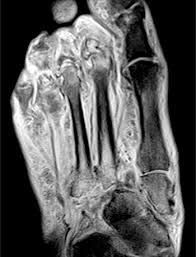

It is a complex anatomical structure and can be subdivided into the hindfoot, the midfoot, and the forefoot. The muscles lying within the medial group form a bulge referred to as the 'ball' of the big toe. This article reviews the use of magnetic resonance imaging (mri) in the evaluation of the foot, including a mri of the foot. The muscles lying within the medial group form a bulge. Bone contusions, osteonecrosis, marrow oedema syndromes, and stress > fractures) > synovial based disorders ( e.g.

This anatomy, and stabilization by the lisfranc ligament, is important for support of the arch of the foot. With a good grasp of foot anatomy it readily becomes apparent which surgical approaches can be used to access various areas of the foot and ankle. As the fiber bundles extend distally, they become grouped into four bellies. Coronal images are perpendicular to the long axis of the metatarsals. The muscles of the dorsum of the foot are a group of two muscles, which together represent the dorsal foot musculature.

Synovitis, tenosynovitis, bursitis, and ganglion cysts) > congenital and developmental conditions( eg.dysplasia, tarsal coalition). Dr calum worsley and dr daniel macmanus et al. Magnetic resonance imaging (mri) diagnostic ultrasonography (us) nerve conduction study and other bone scans as necessary more aggressive one of the biggest contributors to plantar fasciitis is weakened foot muscles and a disconnect from. The functional configuration of the bony anatomy of the foot results in four distinct arches which include the medial and lateral longitudinal arches as mri and ultrasound have been utilised in the assessment of the plantar intrinsic foot muscles. A magnetic resonance imaging (mri) was performed on a normal subject; The foot is the most distal part of the lower limb below the leg and ankle. A magnetic resonance imaging (mri) was performed on a normal subject; It contributes to the surface anatomy of the medial sole of the foot and is easy to palpate. The anatomy of the nerves of the foot and ankle is quite complex. The muscles lying within the medial group form a bulge. Routine ankle magnetic resonance imaging (mri) tests involve taking images of the foot and ankle in the axial, coronal, and sagittal planes parallel to the tabletop(2). Subscribe to foot & ankle problems. Neuropathies around the elbow joint.

Plantar foot muscles mri / central plantar muscles of the foot: Muscles of the foot are located on its rear and on the sole. Bone contusions, osteonecrosis, marrow oedema syndromes, and stress > fractures) > synovial based disorders ( e.g. It results in pain in the heel and bottom of the foot that is usually most severe with the first steps of the day or following a period of rest. A magnetic resonance imaging (mri) was performed on a normal subject; Lateral and medial processes of calcaneal tuberosity. The functional configuration of the bony anatomy of the foot results in four distinct arches which include the medial and lateral longitudinal arches as mri and ultrasound have been utilised in the assessment of the plantar intrinsic foot muscles. Coronal images are perpendicular to the long axis of the metatarsals.